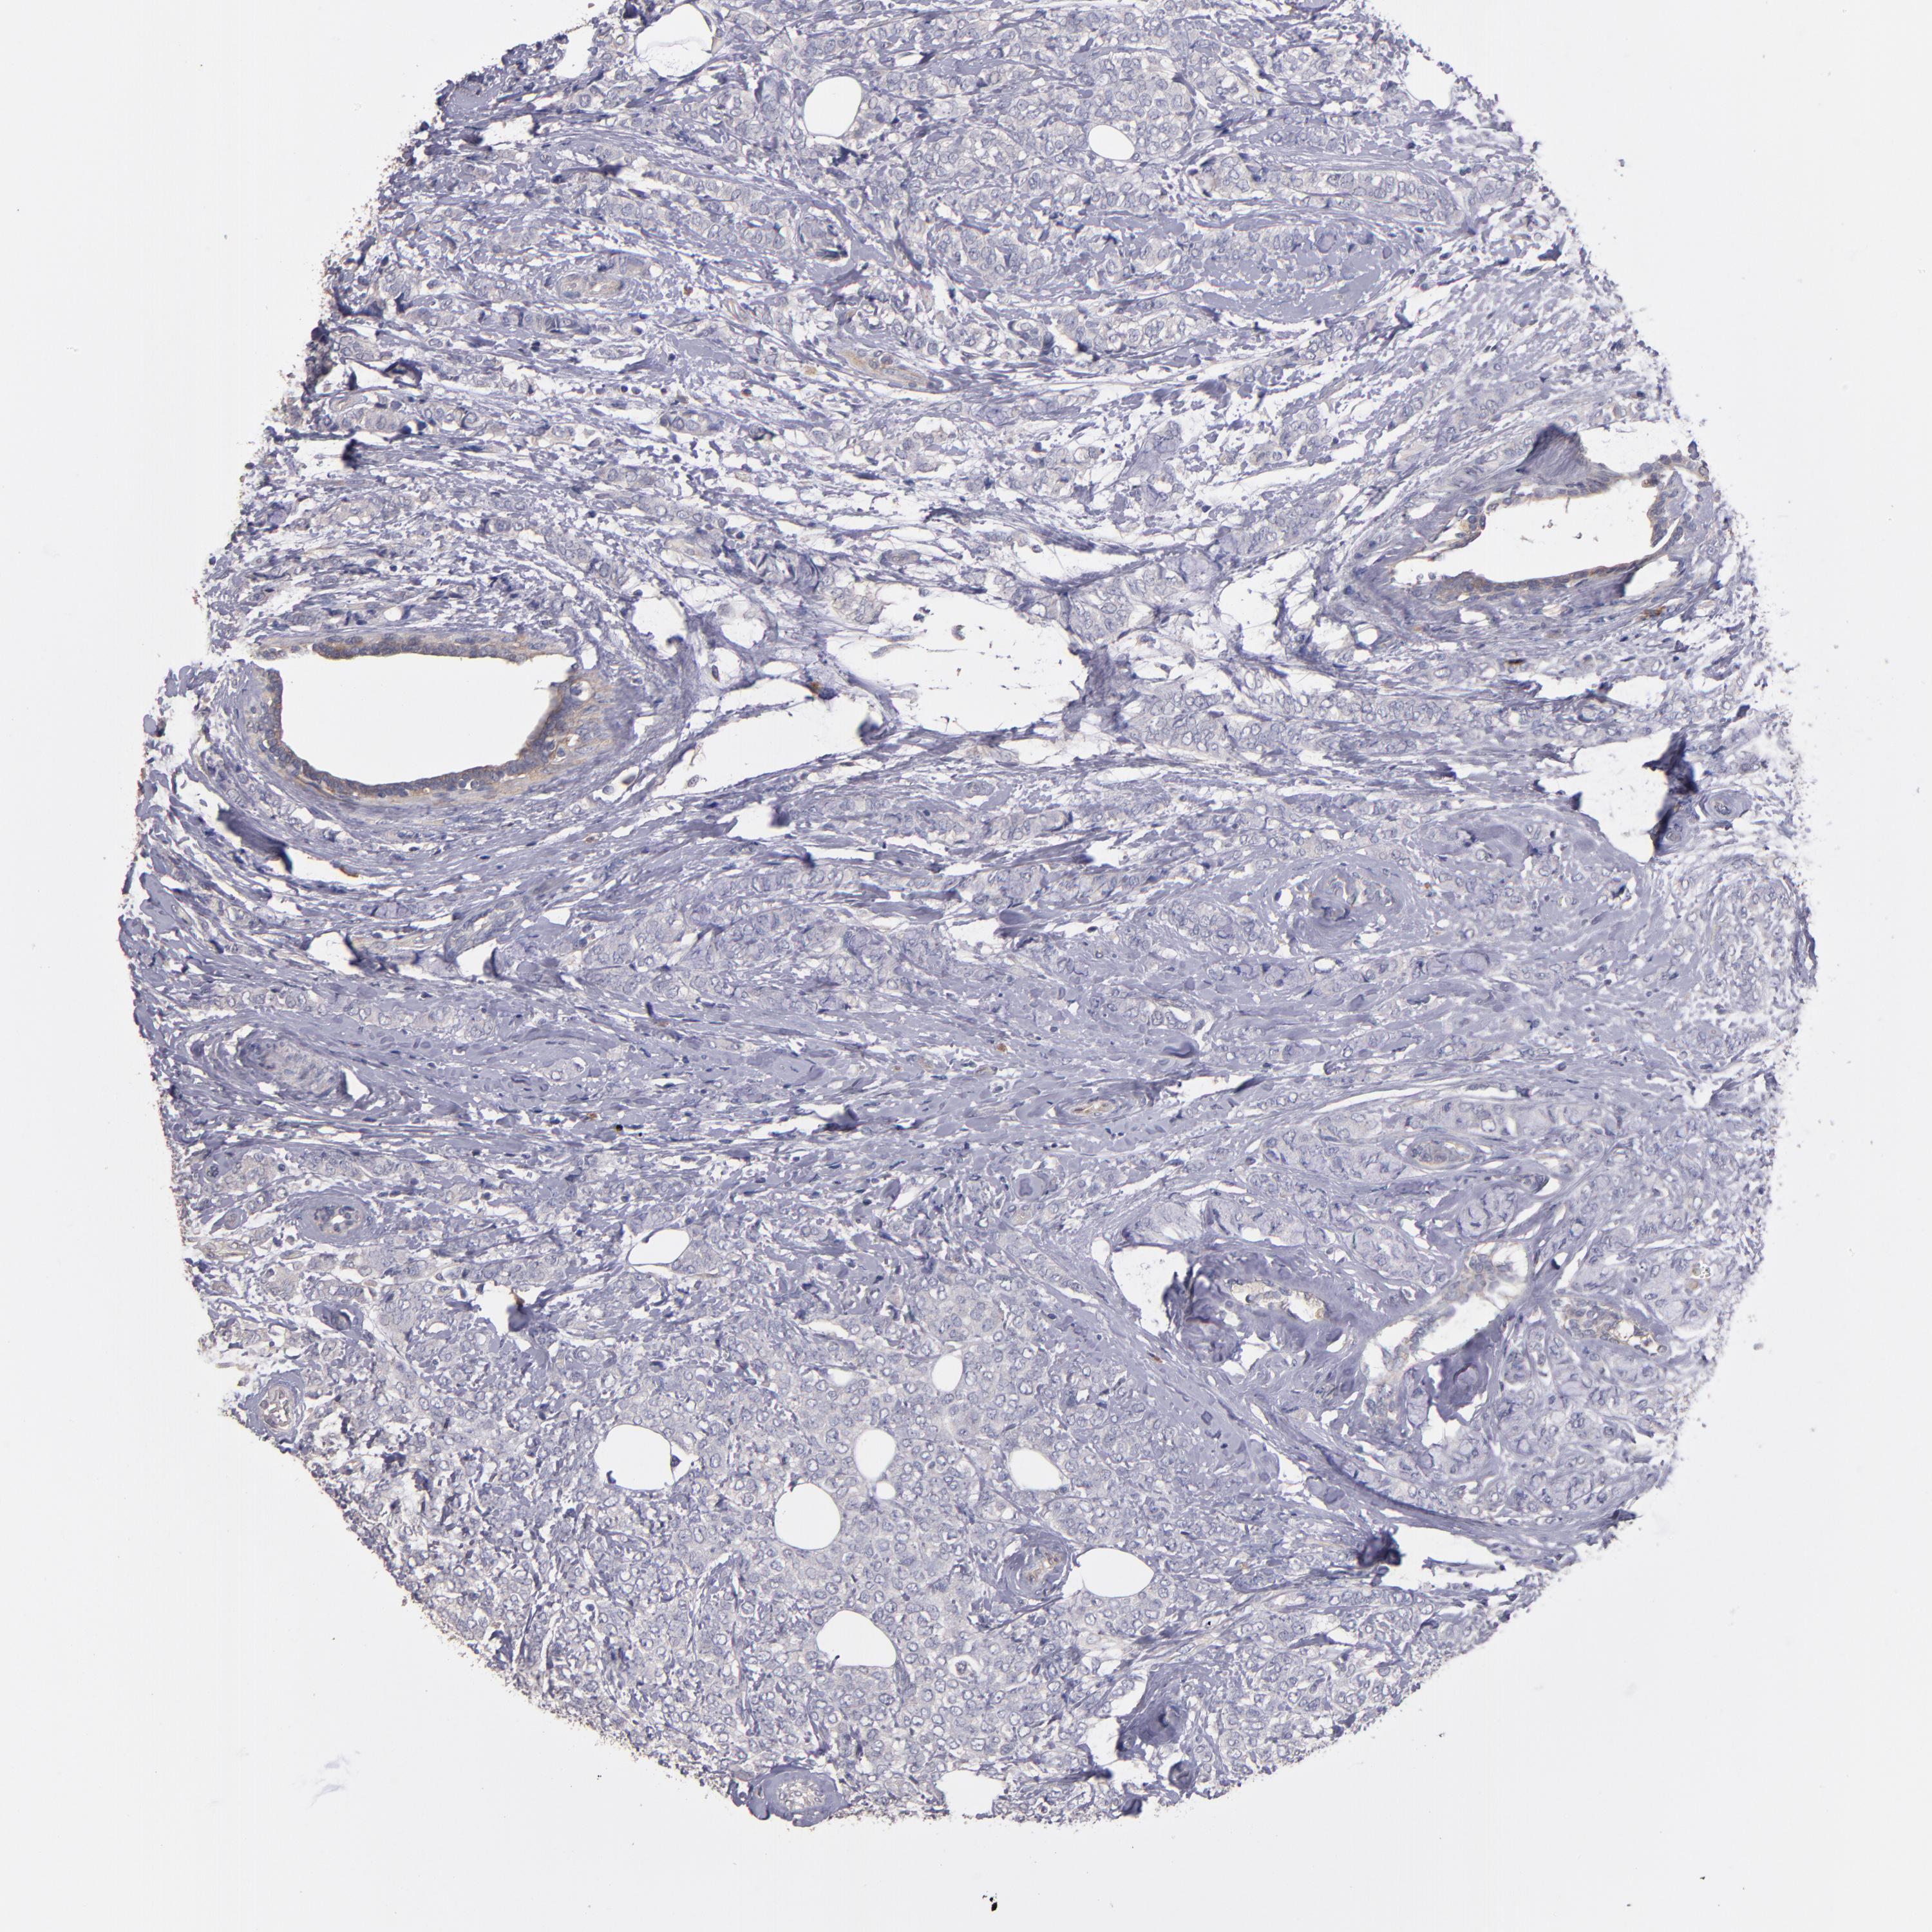

CANCER BREAST CANCER Show tissue menu

BRCA TCGA BRCA VALIDATION PROTEIN EXPRESSION